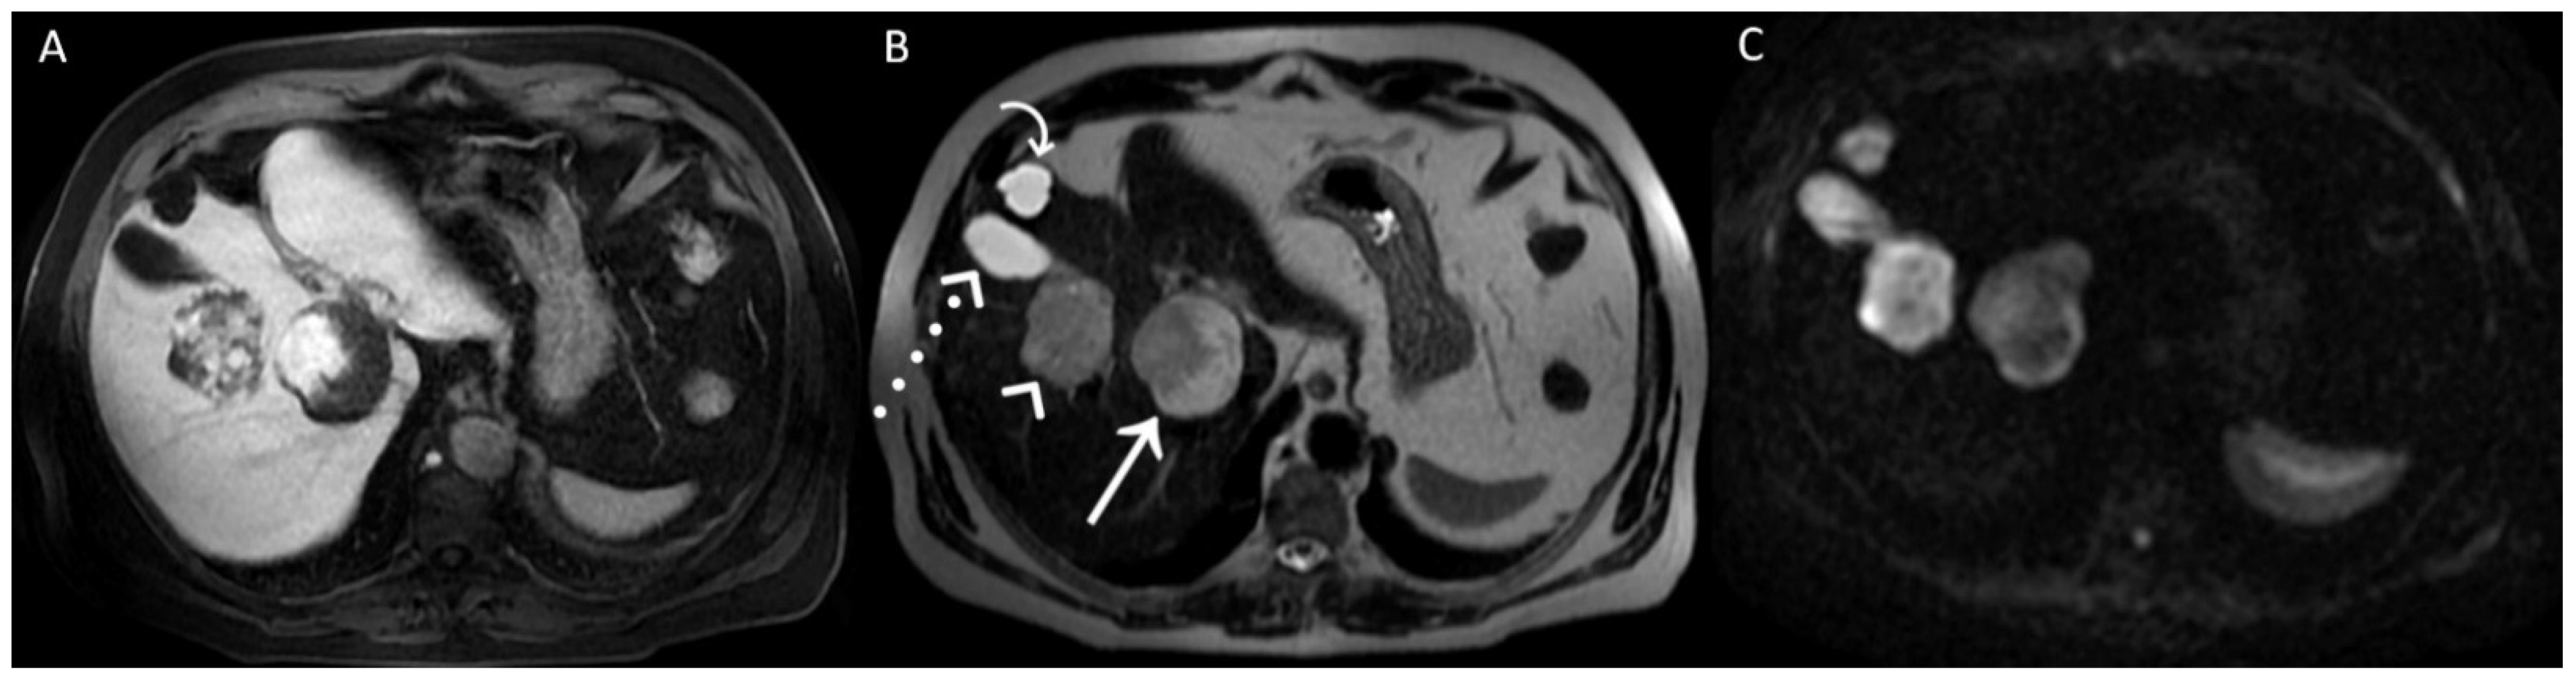

Figure 3.

A posteriori, a perfect correspondence between the contrast agent globular enhancement on Axial T1-weighted fat saturated images in delayed phase (A) and the relatively hypointense areas on post-contrast T2WI (B) and DWI (C) was evident. Furthermore, the largest and deepest lesion showed a relatively hypointense area on DWI, larger than that on T2WI, due to later acquisition of DWI and progressive centripetal contrast filling of the lesion. On T2WI (B), we can also appreciate the comparison between the signal hyperintensity of different structures: cavernous hemangiomas (arrow and arrowhead); simple cyst (curved arrow), and gallbladder’s fundus (dotted arrow). T2WI and DWI are usually acquired after the acquisition of vascular phases in the dead time until the acquisition of the hepatobiliary phase to shorten the time-consuming protocols since it was demonstrated that T2WI and DWI acquired after Gd-EOB-DTPA showed a comparable diagnostic capability to pre-contrast T2WI and DWI in the detection and characterization of hepatic tumors [1,2]. In conclusion, when liver lesions of unknown nature must be characterized, with a lack of previous radiological investigations, it could be useful to acquire pre-contrast T2WI and DWI to avoid diagnostic confusion, especially in non-tertiary centers.